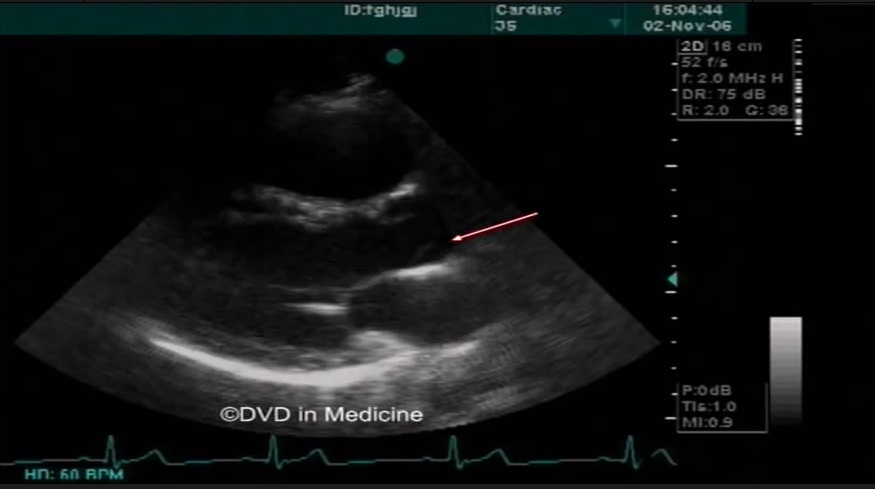

左心声学造影联合负荷超声心动图在冠心病中的临床应用